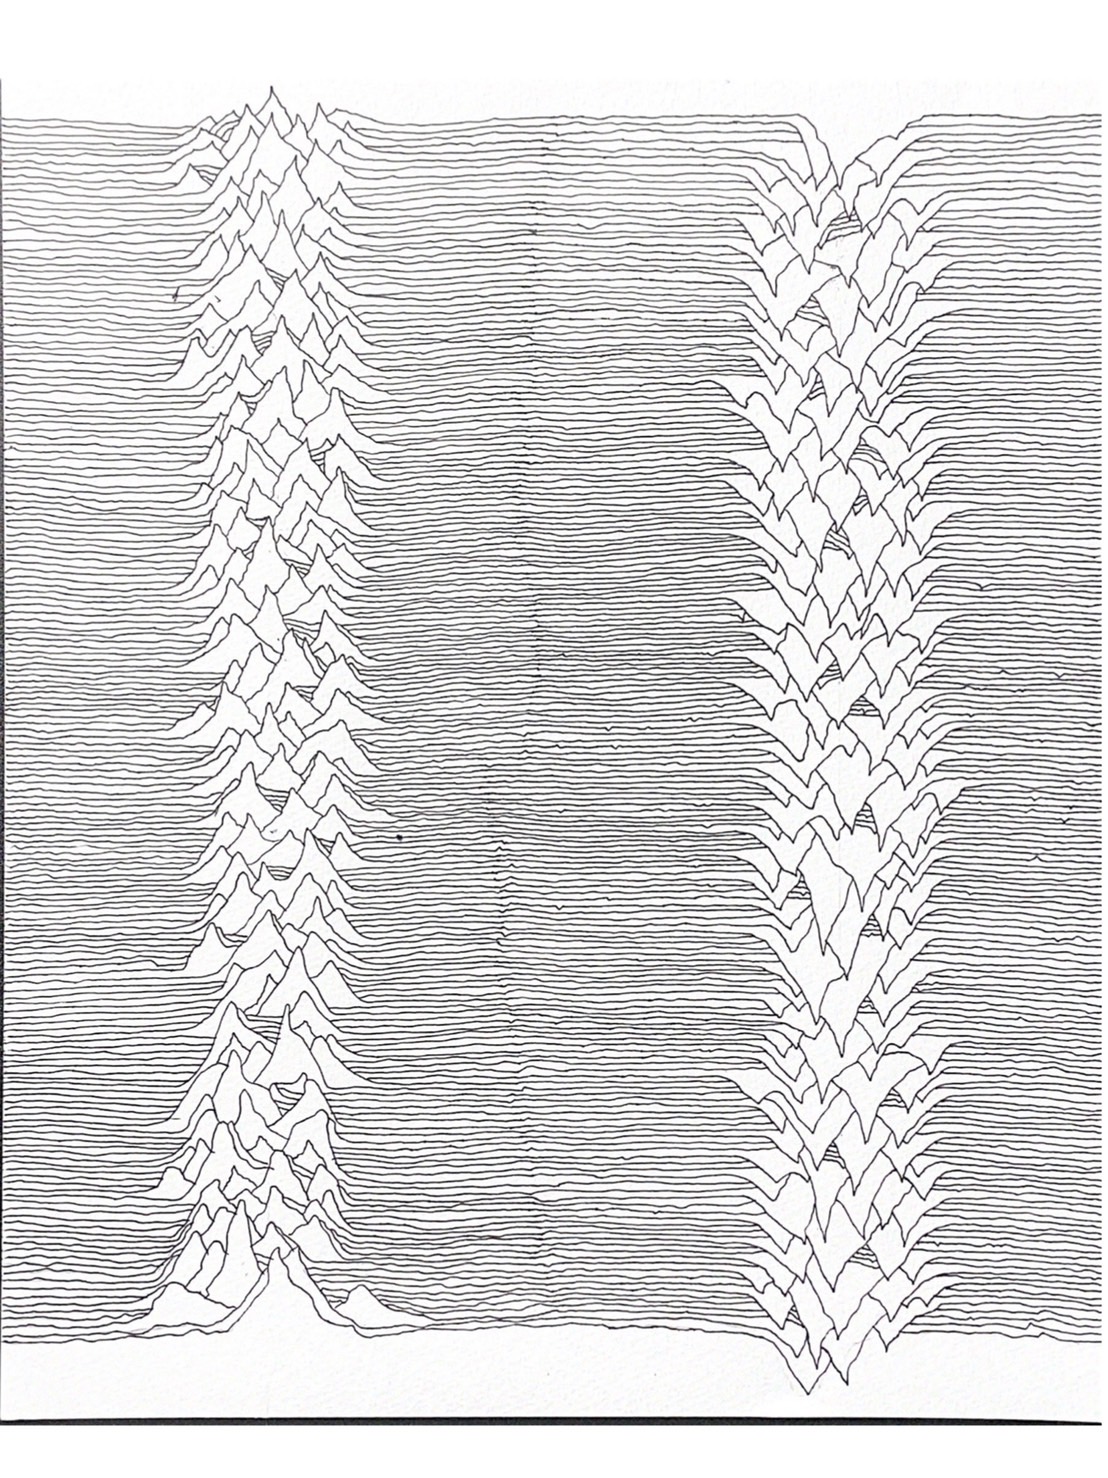

生化学

公衆衛生学

熱帯病寄生虫病学

病理学

呼吸器アレルギー内科

心臓血管外科

放射線科

ハートセンター